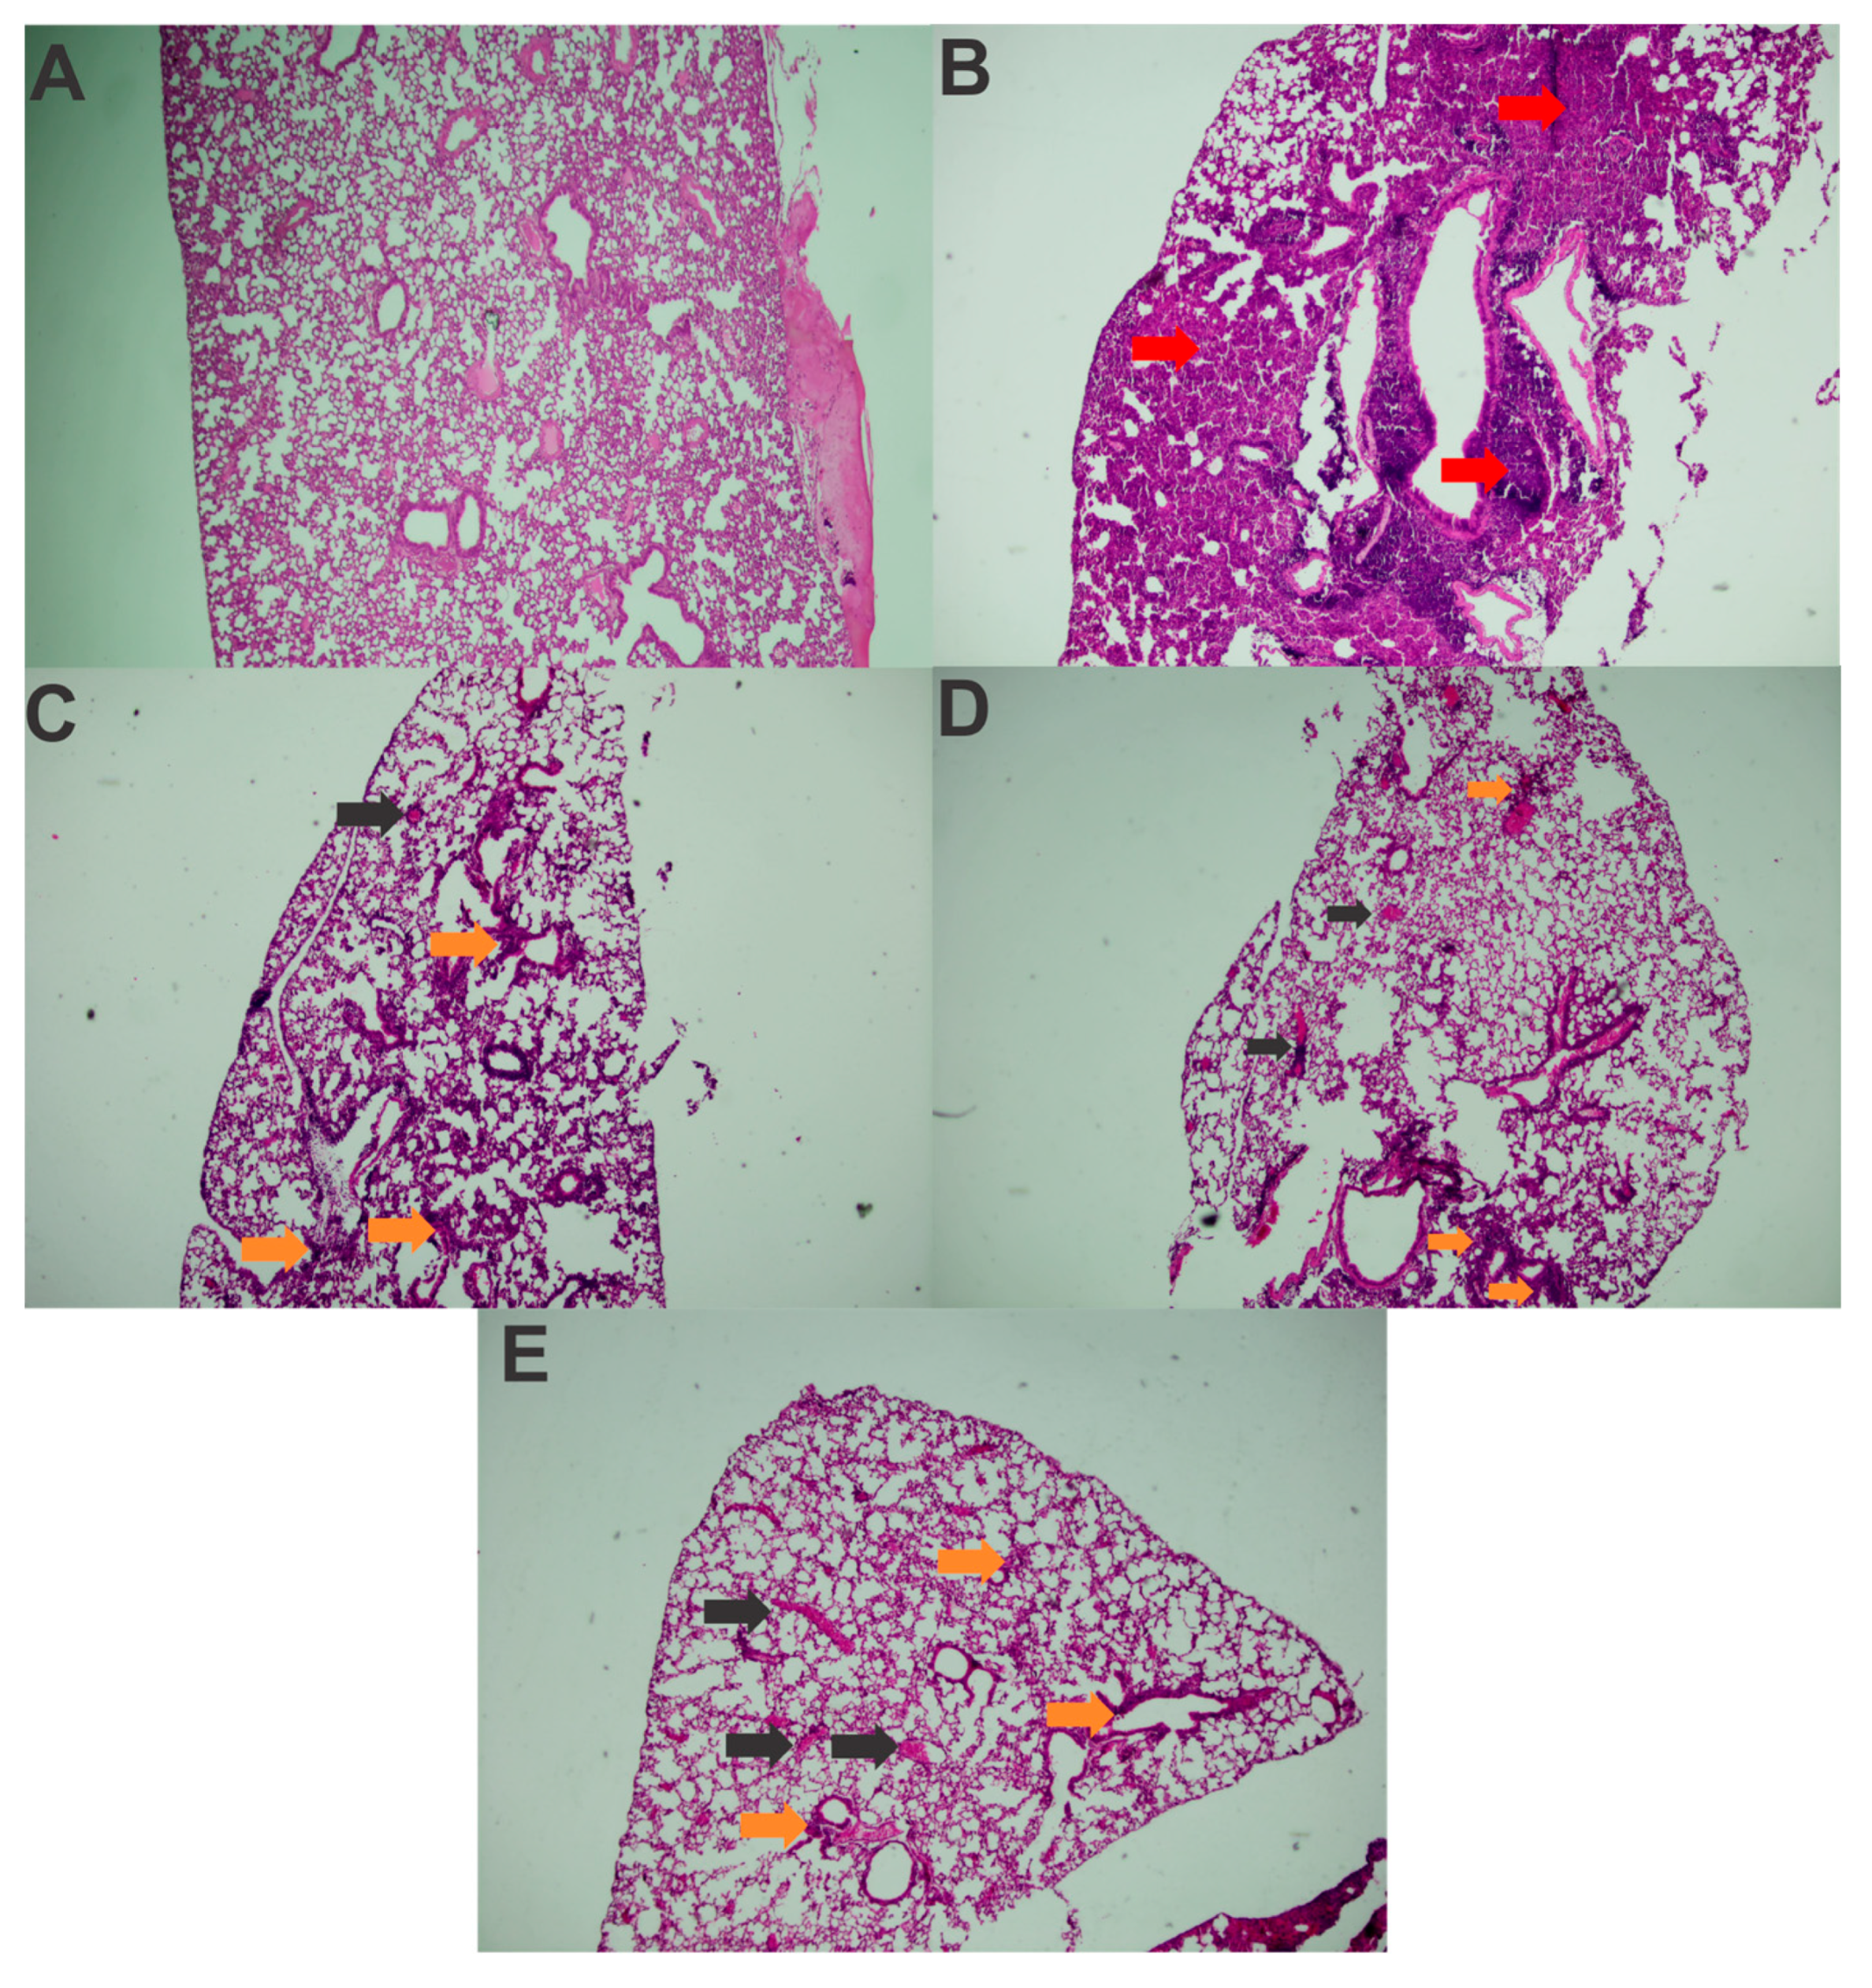

An analysis of the histological slides indicated that, in all challenged groups, the animals exhibited pneumonia, with a predominantly polymorphonuclear diffuse inflammatory infiltrate (Figure 6B–E), in comparison with healthy controls (Figure 6A). Lymphocytes and macrophages were also observed, along with blood vessel congestion and severe hemorrhage, particularly in the challenged control group, where a more pronounced inflammatory infiltrate was present, making it impossible to differentiate the alveolar structures in most of the analyzed fragments (Figure 6B). The inflammation was notably more severe compared to the immunized animals. Dilation and congestion of the vessels surrounding the alveoli were also more abundant in this group.

Figure 6.

Histopathological analysis of the lung tissue from mice before and after challenge with K. pneumoniae (40× amplification). (A) Healthy unchallenged control; (B) challenged control; (C) Immunized with rFimA and challenged; (D) immunized with rMrkA and challenged; (E) immunized with rFimA + rMrkA and challenged. The red and orange arrows indicate intense and moderate inflammatory infiltrates, respectively; black arrows, vessel congestion.

Among the animals that received the recombinant proteins, the inflammatory infiltrate was more localized in the peribronchiolar region. In the lung tissue of the mice that received rFimA, in addition to polymorphonuclear cells, a significant number of lymphocytes and macrophages was also noted (Figure 6C). The mice immunized with rMrkA presented moderate hemorrhage and vessel congestion in the lungs, but the alveolar structures were identifiable in most analyzed fields (Figure 6D).

In the slide from the animal that received the rFimA and rMrkA mix, the inflammatory infiltrate included polymorphonuclear cells, macrophages, lymphocytes and plasma cells (Figure 6E).

The challenged control also showed higher inflammatory and tissue damage scores in comparison with the immunized and challenged mice (Table 1). More specifically, this group showed increased signs of polymorphonuclear inflammatory infiltrate, loss of alveolar structure, congestion and pulmonary hemorrhage when compared to the mice who were immunized before challenge. As expected, no signs of inflammation or tissue damage were found in healthy, unchallenged controls.

Overall, these findings suggest a reduction in the diffusion and intensity of the inflammatory infiltrate in the lung parenchyma following immunization with rFimA and/or rMrkA compared to the control group.